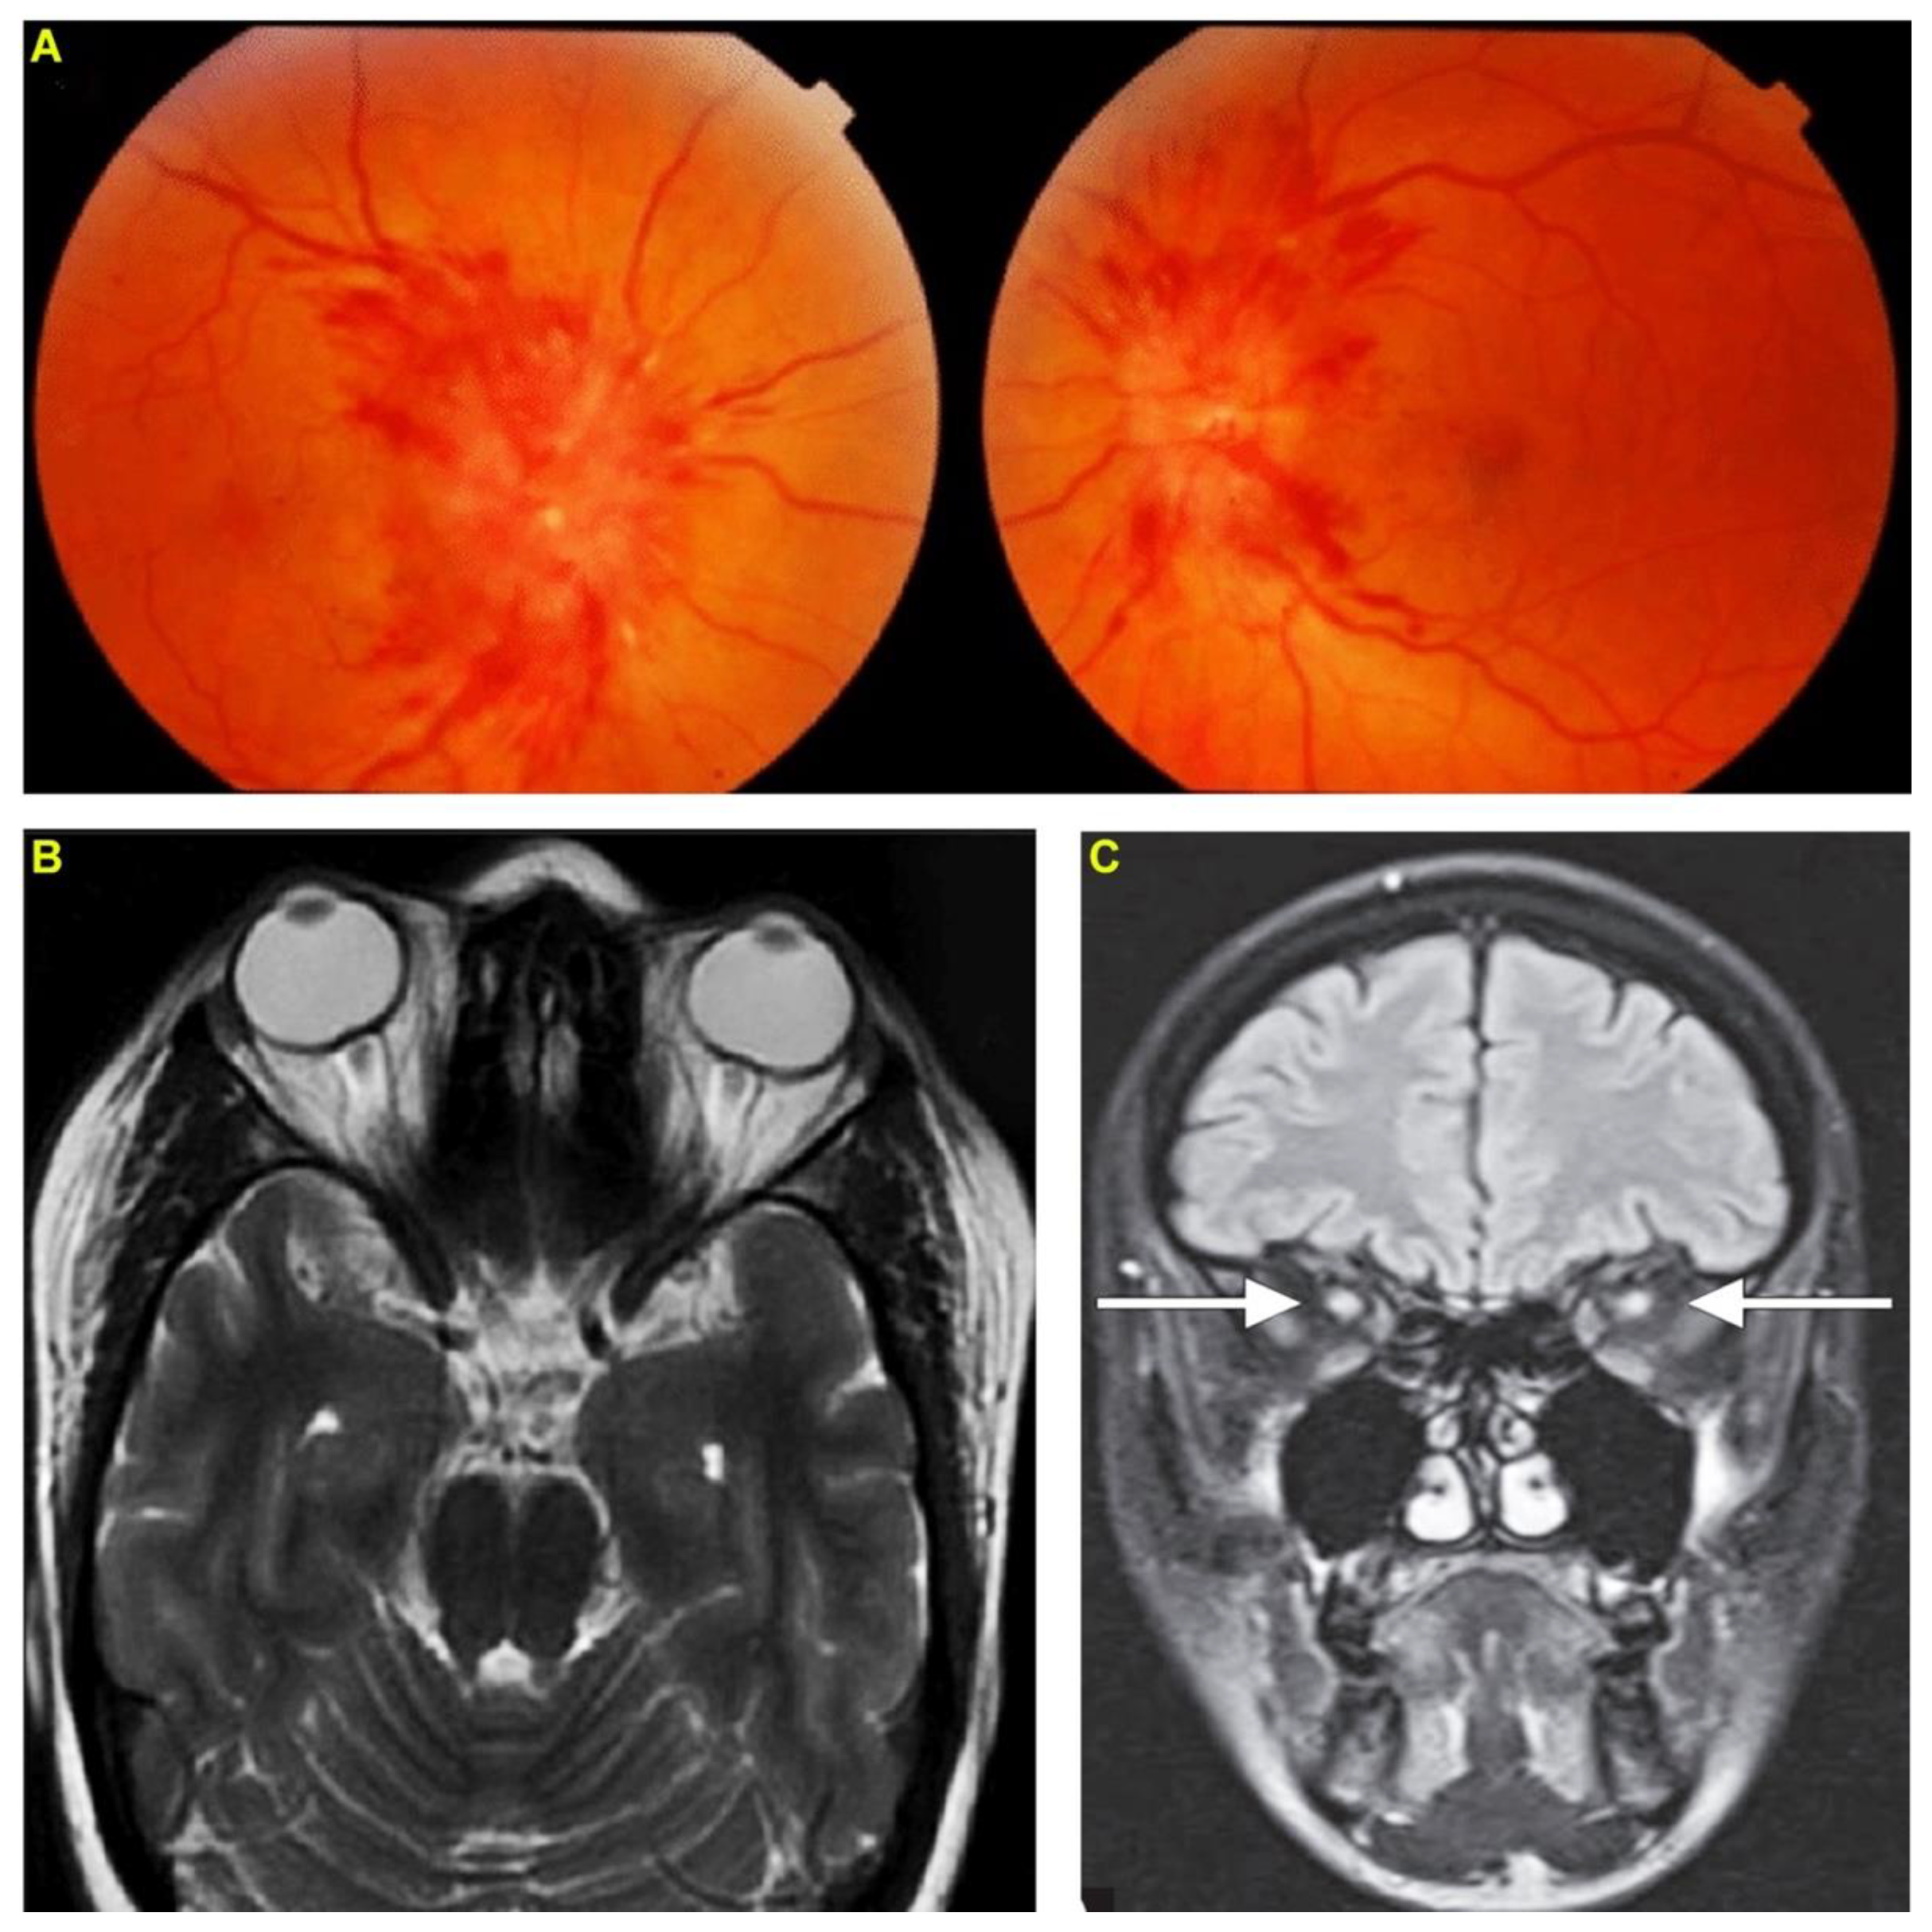

2. Case Report 1: Indian Cobra-Induced Optic Neuritis

3. Case Report 2: Common Krait-Induced Optic Neuritis